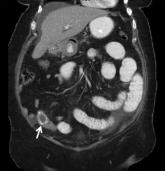

ArticleSmall Bowel Obstruction by Gallstone IleusAuthor:Akshra Verma, MD, MSPublish date: January 26, 2010Read More